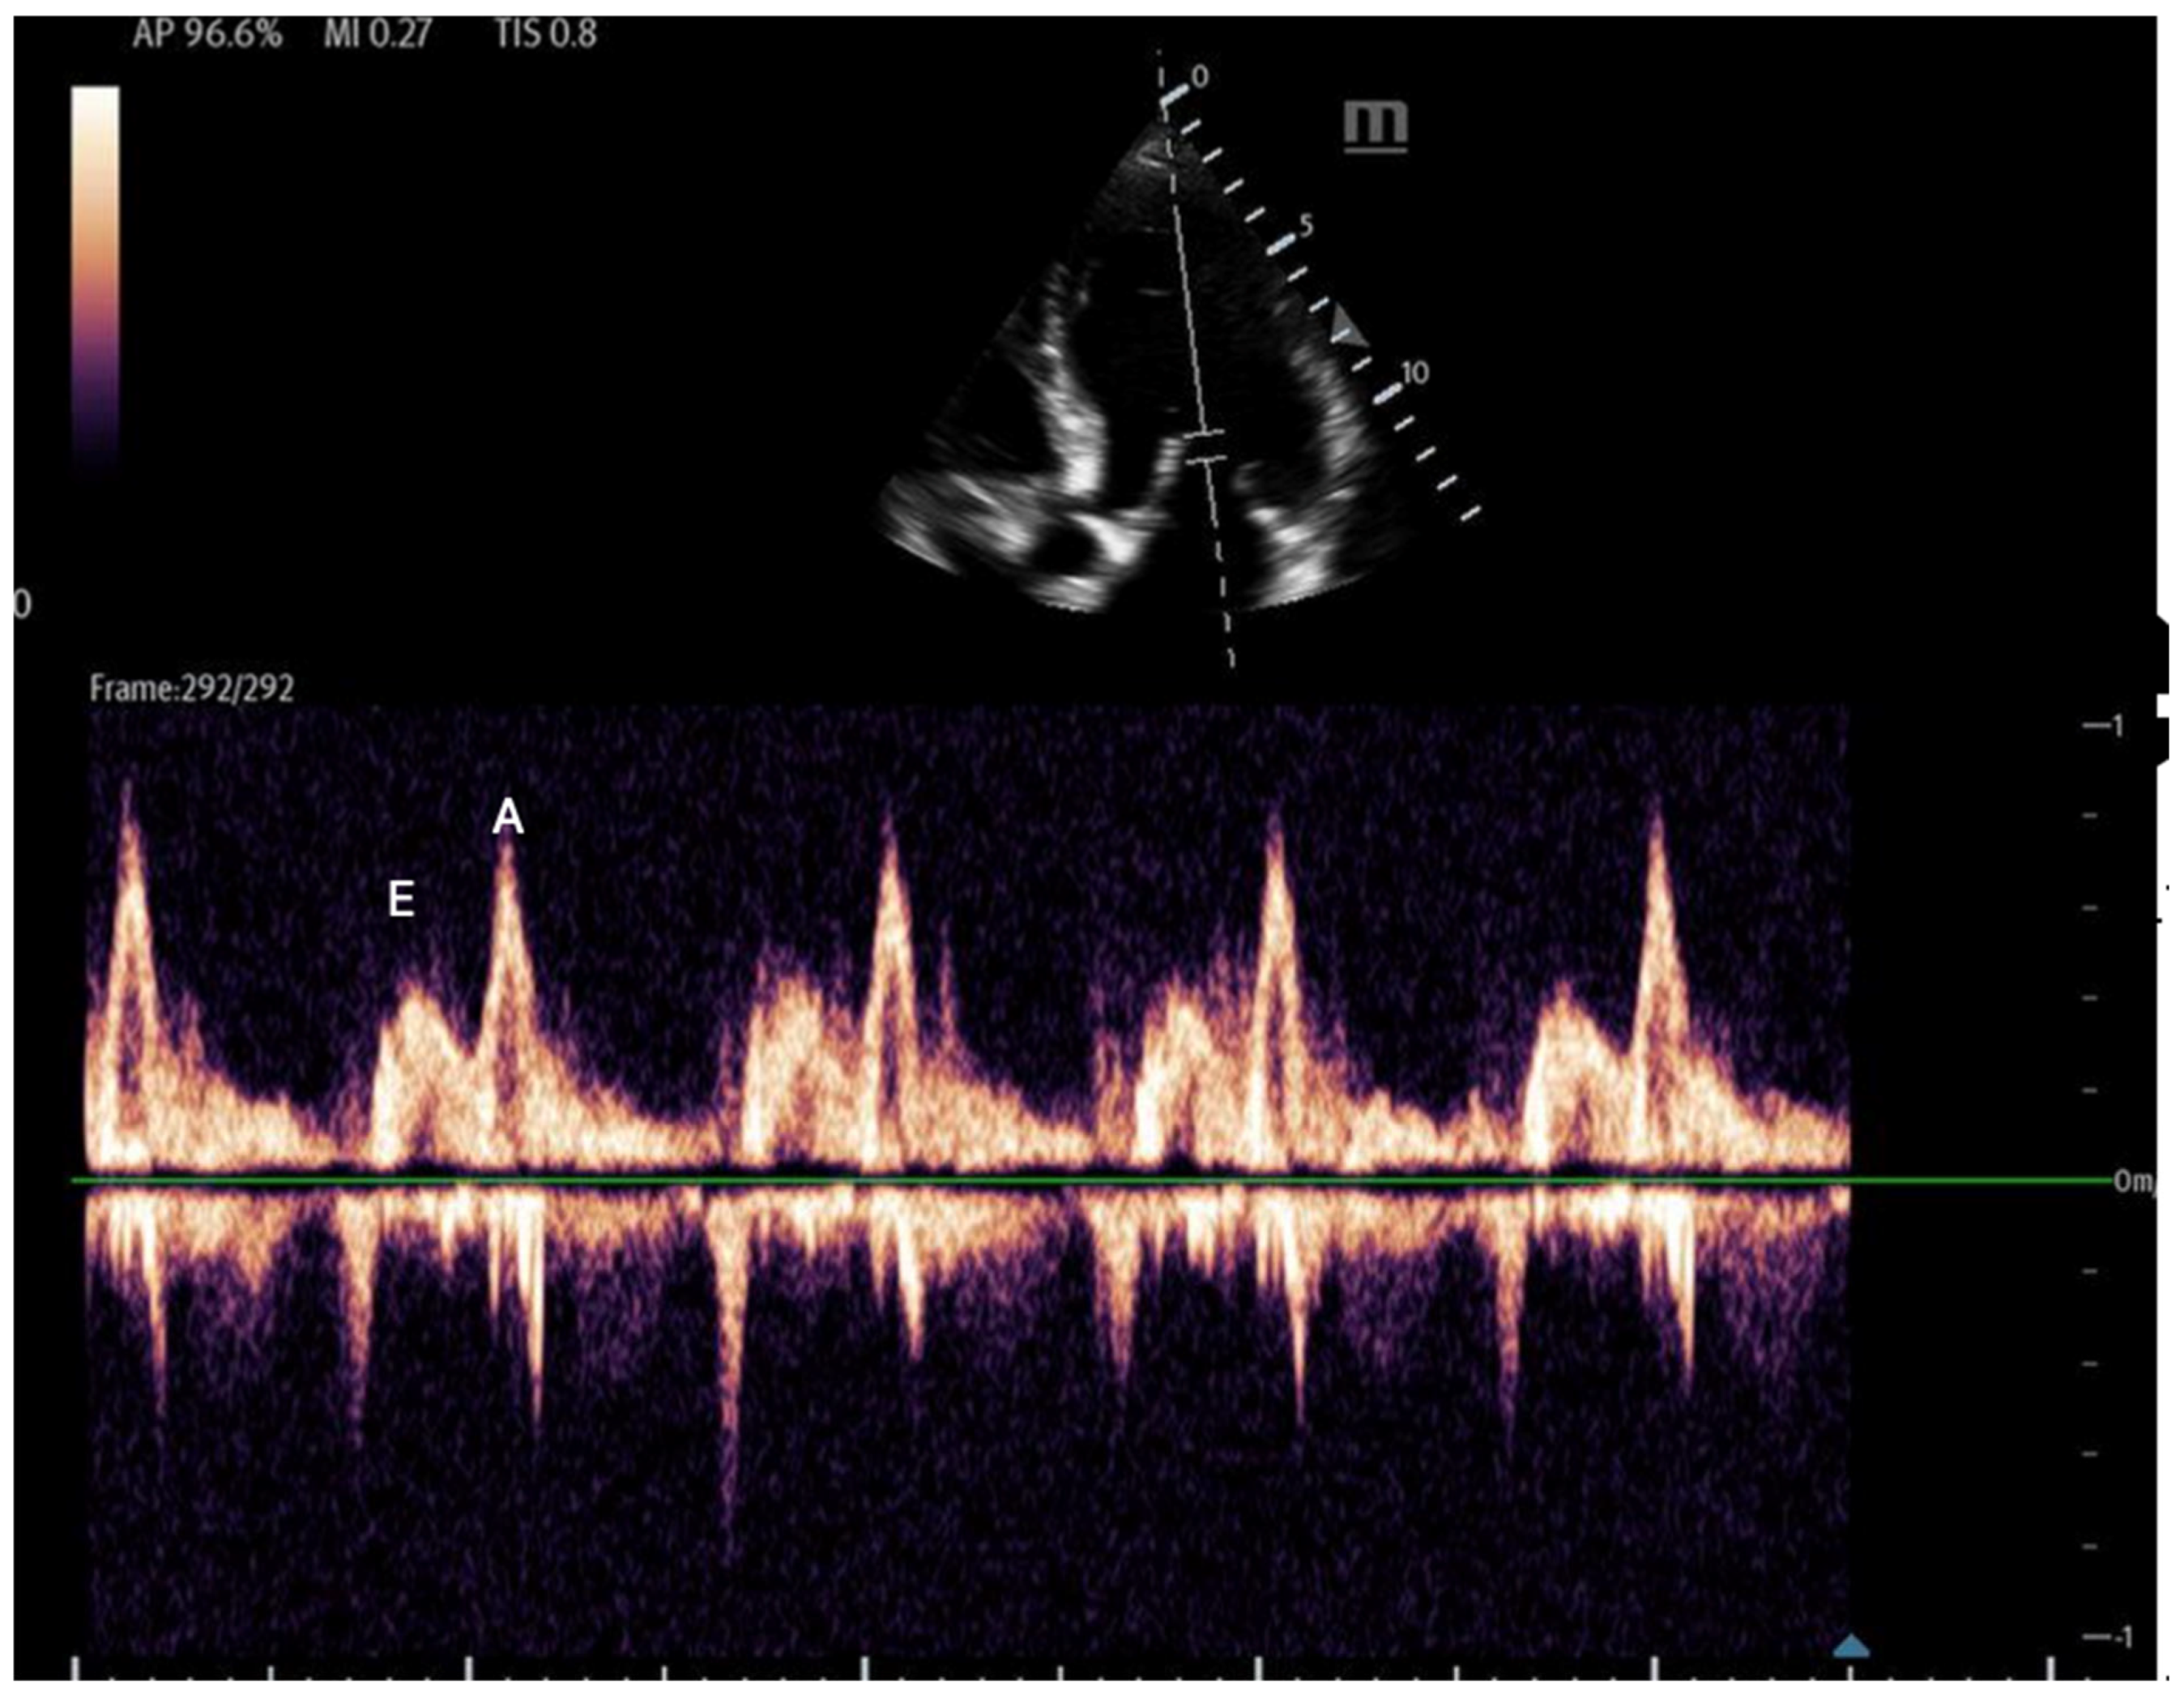

- Mitral inflow: Assessed via pulsed-wave (PW) Doppler at the mitral valve tips in the apical four-chamber view, this measures the blood flow velocities entering the left ventricle as an upward deflection of the PW Doppler signal. The resultant E and A waves are then evaluated for their ratio (Figure 14).

Figure 14. Mitral inflow with PW Doppler gate at mitral valve tip (E and A waves). - Tissue Doppler: Measures myocardial movement during diastole using tissue Doppler at the septal annulus. The E/e′ ratio is calculated from the recorded e′ wave (Figure 15).